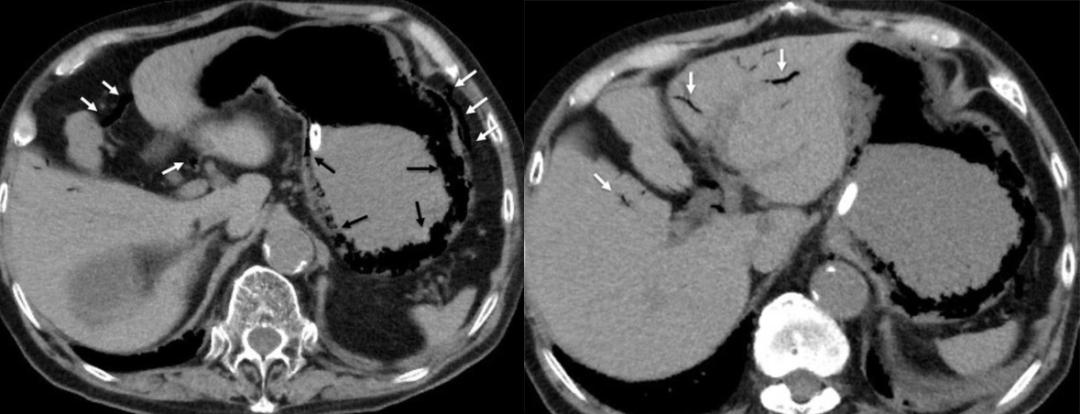

老年女性,腹痛、呕吐就诊。CT 平扫示胃腔扩张,十二指肠降部腔内见高密度结石。

老年女性,右上腹疼痛、呕吐。CT 增强示十二指肠球部结石,十二指肠球部及胆囊相通,存在瘘。